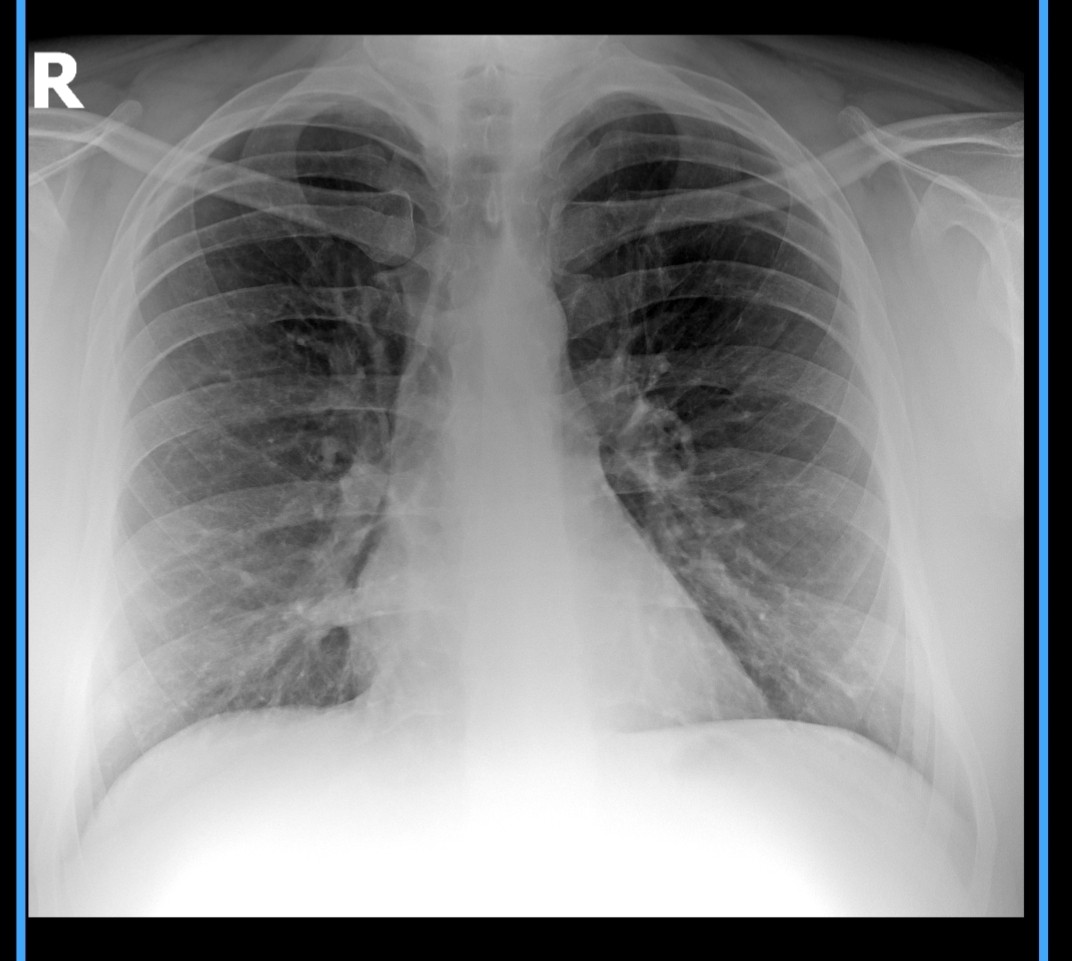

Рентген легких проверить снимок

Пол: Мужской

Возраст: 31 год

Добрый день, мне 31 год. Сделал рентген лёгких, сказали что все хорошо лёгкие здоровые, но одышка беспокоит, прикрепляю снимок, пожалуйста посмотрите снимок скажите точно с легкими все хорошо? Чтоб ошибки не было. Спасибо